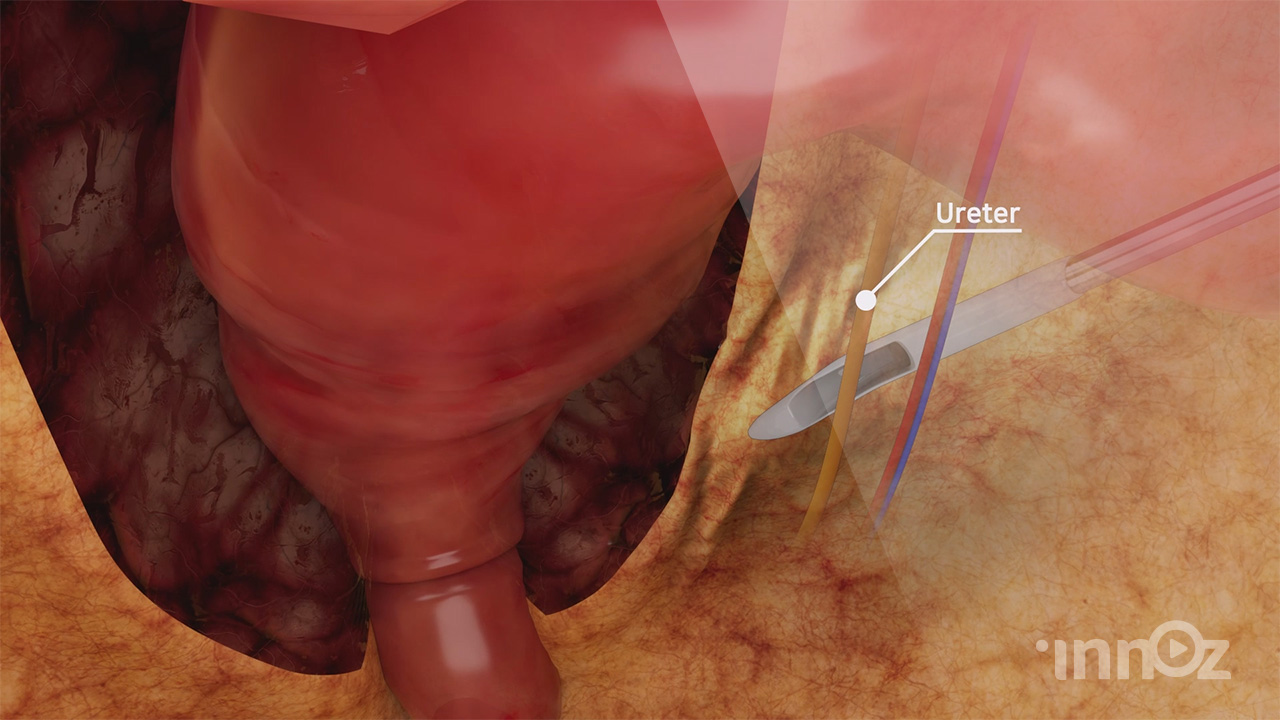

제일메디칼

제일메디칼

제일메디칼

제일메디칼

제일메디칼